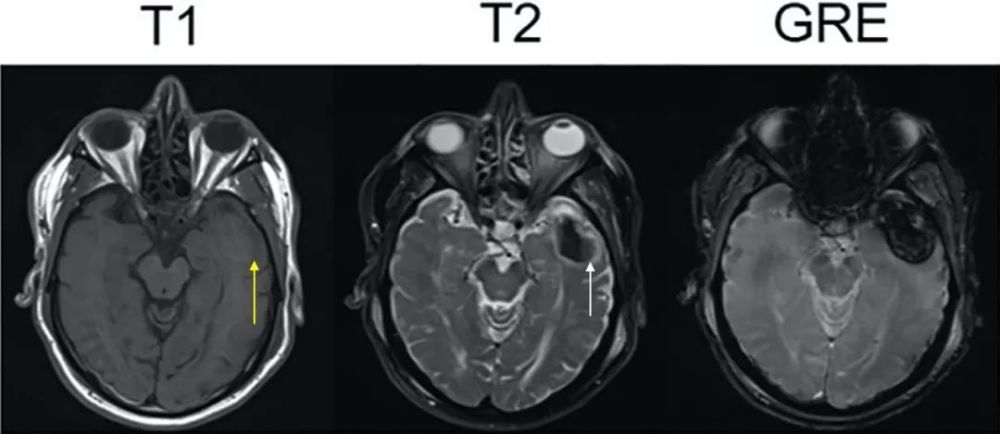

这一时间红细胞的细胞膜保持完整 , 细胞内的氧合血红蛋白失去氧气变成脱氧血红蛋白 , 这一变化由血肿外周向中心逐渐发展 。 脱氧血红蛋白为顺磁性 , 但其疏水 , d>0.3纳米 , 故不影响T1弛豫 , 无“造影剂增强”效应 , T1像较前变化不明显;红细胞完整 , 脱氧血红蛋白在血肿内被分隔在一个个细胞内 , 构成磁场不均一 , 于是产生局部磁敏感效应 , 缩短T2 。

所以急性期血肿T1像呈等或稍低信号 , 外周环绕低信号水肿带(图3:黄箭) , T2像呈低信号 , 其外周环绕高信号水肿带(图3:白箭) 。

图3 急性期脑出血核磁(Rima S. Rindler, Neurosurgery)